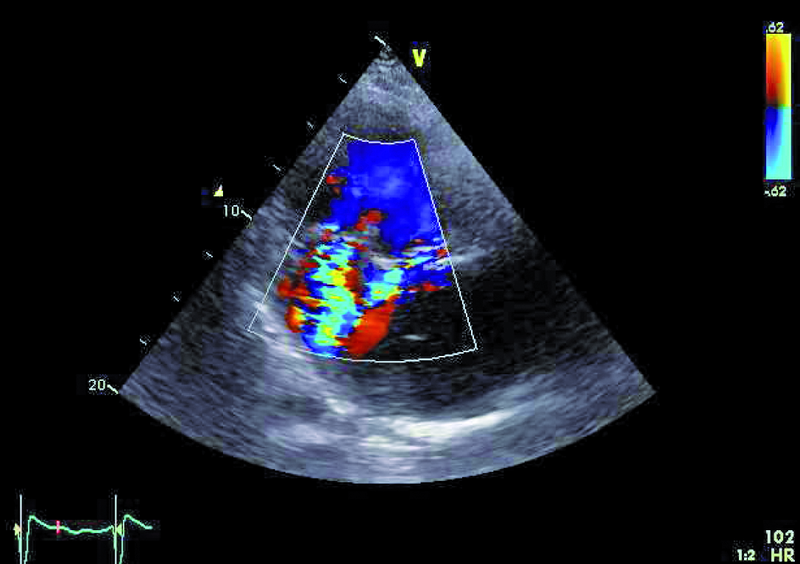

Mężczyzna, lat 31, z wrodzoną wadą serca o typie serca jednokomorowego, zastawkowego i podzastawkowego zwężenia tętnicy płucnej przeszedł w siódmym roku życia zabieg korekcji wady metodą Fontana-Linsa w ośrodku za granicą. Chory od kilku lat gorzej tolerował wysiłek. Rozpoznano napadowe, a następnie utrwalone migotanie przedsionków. Zdarzały się także obrzęki kończyn dolnych, powiększenie obwodu brzucha. Chory negował występowanie sinicy. W badaniu fizykalnym stwierdzono u niego szmer holosystoliczny nad sercem (3/6 w skali Levina), płyn w jamie opłucnej oraz wodobrzusze. Zwrócono uwagę, że w ostatnich latach saturacja spoczynkowa zmniejszyła się z 97 do 90%, a maksymalne zużycie tlenu w teście ergospirometrycznym wyniosło 13,8 ml/kg/min, co stanowiło 31% wartości należnej dla płci i wieku. Stwierdzono silnie wyrażone cechy zespołu enteropatii z hipoproteinemią. W chwili hospitalizacji leczony był dwoma środkami moczopędnymi, beta-adrenolitykiem oraz inhibitorem ACE. Otrzymywał także leczenie przeciwkrzepliwe. Wobec złego stanu ogólnego pacjenta wykonano cewnikowanie serca, stwierdzając ciśnienie w prawym przedsionku 13 mm Hg, średnie ciśnienie w tętnicach płucnych 14 mm Hg, opór płucny 0,2 j.W. Prawy przedsionek był w badaniach istotnie powiększony. Stwierdzano także poszerzenie żyły głównej dolnej (do 36 mm) z cechami samoistnego kontrastowania.

Operację Fontana, będącą rodzajem zabiegu paliatywnego, wykonuje się w celu korekcji zaburzeń hemodynamicznych towarzyszących wspólnej komorze. Celem operacji jest zmniejszenie przeciążenia objętościowego komory, ponieważ otrzymuje ona napływ zarówno z żył płucnych, jak i systemowych. Jest wiele rodzajów serca jednokomorowego. Najczęściej spotyka się zespół z atrezją trójdzielną, niedorozwojem lewej komory, zarośnięciem tętnicy płucnej, dwunapływową komorą lewą, dwuodpływową komorą lewą lub prawą. W podanym przykładzie można wyróżnić dwie zastawki przedsionkowo-komorowe, a więc krew wpływa do wspólnej komory (anatomicznie lewej) zarówno przez ujście trójdzielne, jak i mitralne, co dowodzi obecności komory dwunapływowej (ryc. 1-4). Celem operacji w tym wypadku było nie tylko oddzielenie spływu z żył systemowych, ale także zwiększenie całkowitej objętości krwi płynącej przez łożysko tętnic płucnych. Jak oceniać echokardiograficznie pacjenta po operacji metodą Fontana? Nie dziwi, że wspólna komora jest powiększona (ryc. 1, 2, 5), przerośnięta (ryc. 1, 2) i wykazuje upośledzoną kurczliwość. Jeśli wykształcone są dwie zastawki przedsionkowo-komorowe, należy ocenić każdą z nich, ponieważ fale zwrotne powodowane przez zastawki mogą zwiększać objętość komory i niekorzystnie wpływać na funkcję kurczliwą mięśnia. Niedomykalność zastawek przedsionkowo-komorowych (w podanym przykładzie umiarkowana [ryc. 5]) może także zwiększać ciśnienie w jamie lewego przedsionka, co zmniejsza konieczny dla wytworzonego zespolenia gradient ciśnień: żyła systemowa – tętnica płucna – lewy przedsionek. Wynikiem zmniejszania się gradientu może być narastanie ciśnienia w kanale Fontana (ryc. 1-3), pojawienie się hepatomegalii, przesięków do jam ciała, zespołu enteropatii z hipoproteinemią. Niemal u wszystkich chorych po operacji Fontana obserwuje się poszerzenie światła żyły głównej dolnej ze zwolnieniem przepływu krwi i zjawiskiem samokontrastowania się. Nie zawsze udaje się precyzyjnie uwidocznić morfologię wykonanego zespolenia. W tym wypadku mieliśmy do czynienia z tzw. starym jego rodzajem, polegającym na bezpośrednim połączeniu prawego przedsionka z pniem tętnicy płucnej bezpośrednio (ryc. 6). Metoda taka (Fontana-Linsa) stosowana była w latach 70. i 80. ubiegłego stulecia. W przypadku ciężkiego upośledzenia funkcji kurczliwej wspólnej komory, braku zwężenia w kanale Fontana i wykluczenia istotnych niedomykalności zastawek przedsionkowo-komorowych postępowaniem z wyboru pozostaje zabieg przeszczepienia serca, do którego chory został zakwalifikowany.